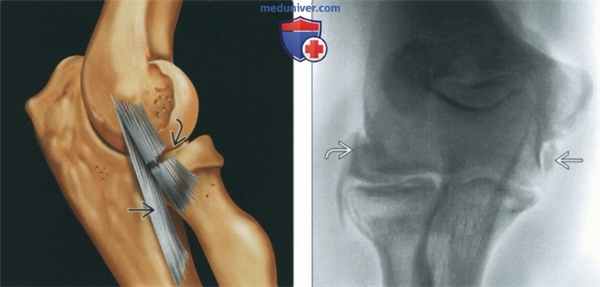

(Слева) Рисунок, латеральная поверхность локтевого сустава: показан разрыв средней трети лучевой коллатеральной связки (ЛуКС). При этом целостность лучелоктевой коллатеральной связки (ЛЛоКС) сохранена.

(Справа) Артрография, передне-задняя проекция: определяются разрывы как ЛуКС, так и ЛЛоКС, обусловленные вывихом. Контрастный препарат скапливается между разорванными концами связок и прилежащими мышцами.